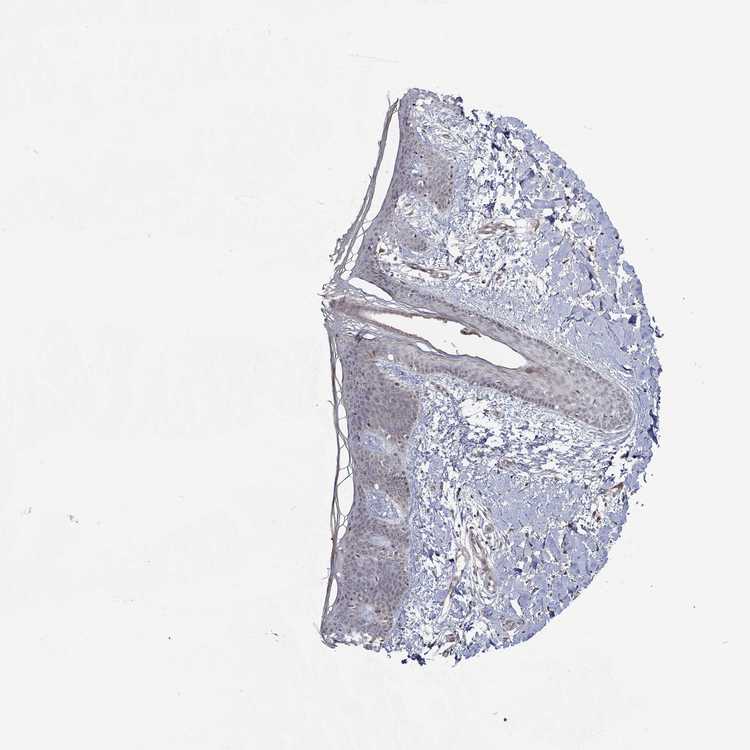

SKIN 1 - Antibody stainingi

Antibody staining in the annotated cell types in the current human tissue is reported as not detected, low, medium, or high, based on conventional immunohistochemistry profiling in selected tissues. This score is based on the combination of the staining intensity and fraction of stained cells.

Each image is clickable and will lead to virtual microscopy that enables deeper exploration of all samples and also displays staining intensity scores, fraction scores and subcellular localization as well as patient and tissue information for each sample.

Antibody HPA076275

Langerhans Not detected

Fibroblasts Not detected

Keratinocytes Low

Melanocytes Not detected

SKIN 2 - Antibody stainingi

Epidermal cells Medium